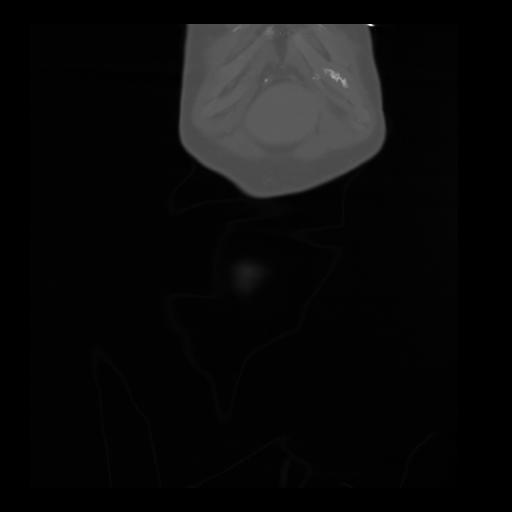

35 CUERPO,CE,Coronal,3.000,CUERPO,Coronal,